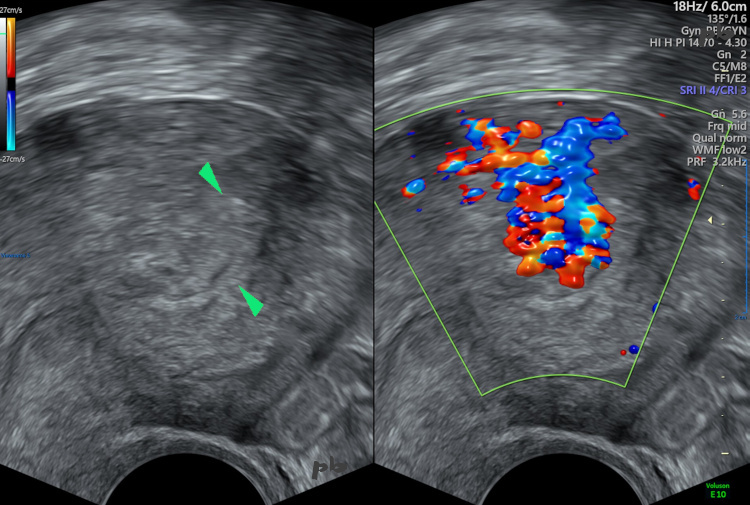

6 – Résidus trophoblastiques

Echographie et doppler – Coupe sagittale.

Muqueuse et cavité utérine (►) très épaissies et hétérogènes, avec effacement de l’interface en postérieur (marqueur supérieur ► sur l’image gauche).

A ce niveau (sur l’image droite), riche vascularisation en doppler, à la fois dans le myomètre et dans la cavité : résidus trophoblastiques avec vascularisation de type utéro-placentaire. On utilise actuellement le terme purement descriptif d’anomalie vasculaire. Il ne s’agit pas d’une malformation artério-veineuse.

Une échographie réalisée 6 semaines plus tard montrait une vacuité utérine, sans aucun traitement.